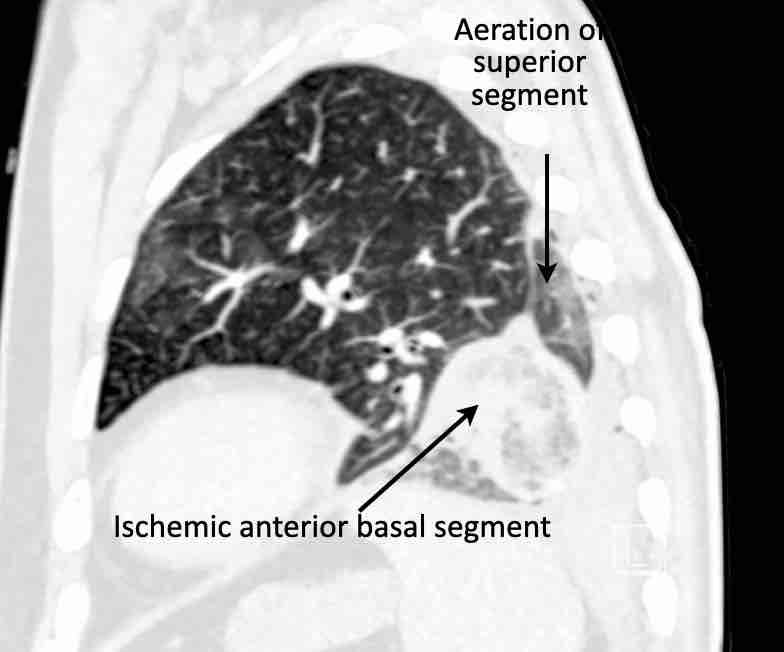

Hình ảnh

Cuộn qua các hình ảnh.

Theo dõi các phế quản của thùy dưới phổi trái cho thấy nhánh phân thùy đầu tiên của thùy dưới phổi trái còn thông; đó là phế quản phân thùy đỉnh.

Các ghim phẫu thuật nằm tại vị trí của các phân thùy đáy sau và đáy bên (LB9/10), vốn thường được cắt bỏ cùng nhau.

Do đó, phân thùy phổi có hình ảnh kính mờ và đông đặc phải là phân thùy đáy trước của thùy dưới phổi trái (LB8).

Động mạch phổi đến phân thùy này cũng không ngấm thuốc cản quang, và bản đồ tưới máu iốt nhấn mạnh thêm tình trạng nhồi máu.

Bệnh nhân đã được phẫu thuật lại và tiến hành cắt bỏ phân thùy bị nhồi máu, với xác nhận qua giải phẫu bệnh.

Trên bản đồ tưới máu iốt, có sự tưới máu ở thùy trên phổi trái và phân thùy đỉnh của thùy dưới phổi trái, nhưng không có sự tưới máu ở phân thùy đáy trước của thùy dưới phổi trái.